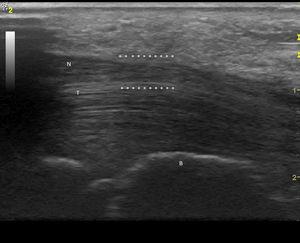

Observación clínicaMujer de 84 años, hipertensa controlada, presentaba desde hace 2 meses lesiones cutáneas en ambas manos de tipo vasculítico asociadas a cianosis del 1.er, 2.° y 3.° dedos, y a dolor intenso que motivaron hospitalización en urgencia por sospecha de vasculitis sistémica. En la anamnesis dirigida, no había elementos de conectivopatía ni consumo de drogas. Recibía enalapril para tratar su hipertensión arterial. En el examen físico destacaban lesiones periungueales, en pulpejos, indicativas de vasculitis, pero llamaba la atención su distribución dermatómica, la severa hipoestesia asociada en el mismo territorio y la importante atrofia de la eminencia tenar, de manera bilateral (fig. 1). El resto del examen era normal; en particular, no había lesiones cutáneas en otras localizaciones y su tensión arterial era normal. Se realizó estudio: hemograma y velocidad eritrocitaria de sedimentación normales, función renal y orina completa normales, factor reumatoideo negativo, anticuerpos antinucleares negativos, perfil ENA detallado negativo, ANCA c y p negativos. La paciente refería de alteraciones de la sensibilidad con parestesias nocturnas y falta de fuerza en manos con tiempo de evolución prolongado, por lo que ya había consultado. Se había hecho el diagnóstico de STC, realizándose una electromiografía de extremidades superiores un año antes. Esta mostraba ya un severo atrapamiento de ambos nervios medianos a nivel de los túneles carpianos, con denervación completa de las eminencias tenares. Se realizó estudio ultrasonográfico de la paciente evidenciando a la entrada del túnel a nivel del pisiforme, un nervio mediano derecho de 17mm2 de área (normal=± 10mm2)1,2 (fig. 2), con presencia central de una arteria mediana remanente (fig. 3). El nervio mediano izquierdo estaba también engrosado, con un área nivel del pisiforme de 18mm2. Ambos nervios aparecían atrapados en el túnel carpiano en los cortes longitudinales (fig. 4).

Corte transversal del nervio mediano en el túnel carpiano: arteria mediana remanente. (Imagen obtenida con ecógrafo General Electrics LOGIC e, con un transductor linear de 8-12 mHz, usando el Doppler de potencia con una frecuencia de 5,0MHz, ganancia de 12, PRF DE 1,2 hHz y filtro de pared de 180Hz).